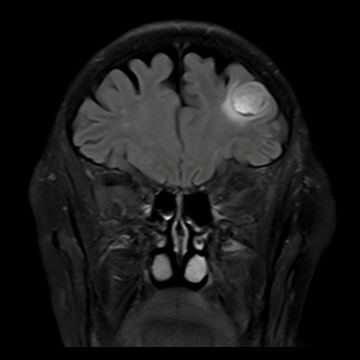

腫瘍

Dark Fluid, 320 matrix

脳腫瘍